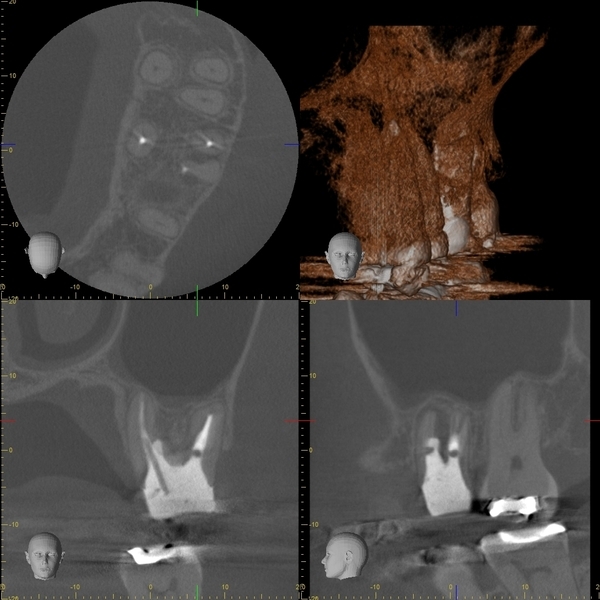

術前のレントゲン写真とCT画像と、お口の中の写真です。下の前歯2本(#31,41)です。

2本の根の周りに黒い影(透過像)があるのが分かります。

術後6ヵ月後のレントゲン写真とCT画像です。

術前にあった根の周りの黒い影は縮小して改善しているのが分かります。